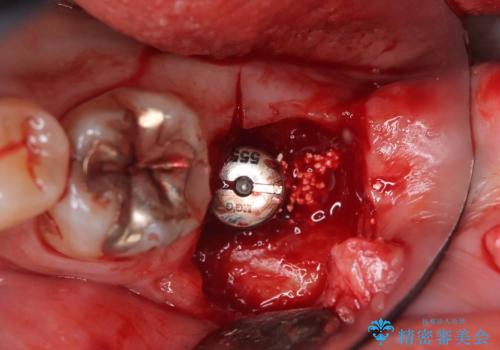

検査の結果、左下7番は歯周ポケットが8mmと深く、レントゲンでも根尖部から骨が溶けている状態が確認されました。エンドペリオ病変と診断し、精密根管治療による保存か、抜歯をしてインプラントで治療するかをご提案したところ、患者様は抜歯・インプラント治療を希望されました。

また、左下6番は銀歯と虫歯を除去した後、見た目や適合性に優れたオールセラミッククラウンで修復を行いました。

インプラントとセラミック治療を組み合わせることで、見た目も自然で噛み心地の良い状態を回復することができ、患者様にも大変ご満足いただけました。